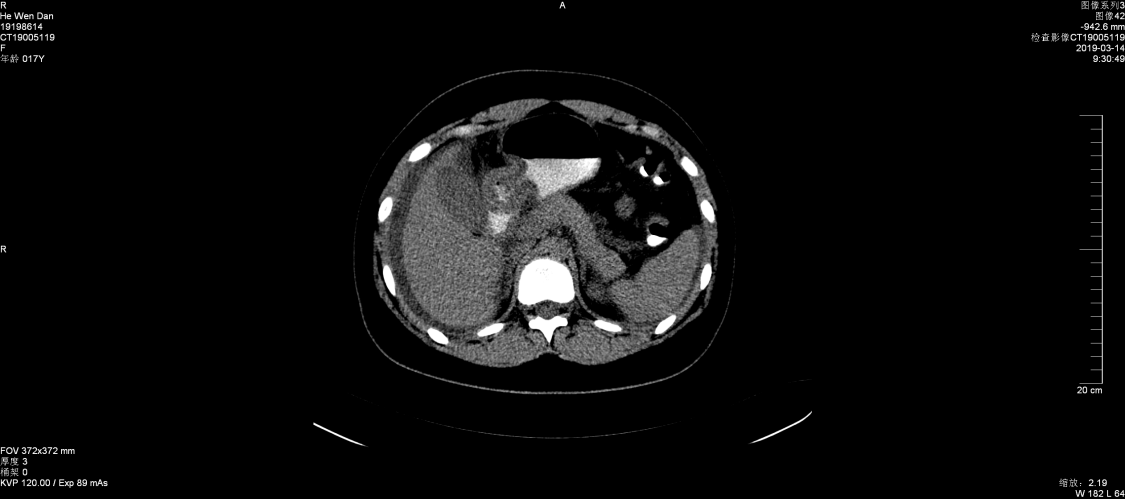

张永红主任查房考虑为嗜酸粒细胞性胃肠炎,组织全科讨论,结合临床表现及检查结果,并排除引起嗜酸性粒细胞增多的疾病,最后诊断为:嗜酸粒细胞性胃肠炎。果断给予强的松30mg一次/日,三天后症状减轻,腹水减少,复查血常规、腹部B超较前好转,一周后患者腹水消失,症状消失,除嗜酸细胞值高以外,血常规正常,痊愈出院。建议病人定期门诊复查,目前激素仍在减量之中......